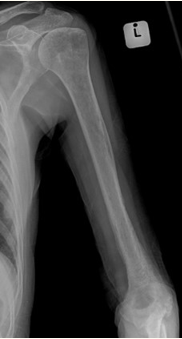

Open fractures, penetrating injuries or bone surgeries can be a direct source of infection resulting in acute osteomyelitis.

Radiographs

Anteroposterior and lateral views of the affected limb. May be normal in early infection. At a later stage periosteal reaction can be seen. Can also identify air around soft tissue suggestive of an infection. Involucrum and sequestrum are features of chronic osteomyelitis.